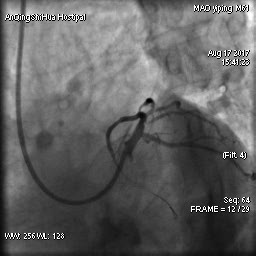

由于毛先生的病變涉及主干分叉,即復(fù)雜的真性分叉病變,為保證分支開口得到良好的開放,術(shù)者采取了操作復(fù)雜的雙支架術(shù)式,先后運(yùn)用掏支架網(wǎng)眼、球囊擴(kuò)張、雙球囊對(duì)吻擴(kuò)張、POT技術(shù)等,實(shí)現(xiàn)了完全血運(yùn)重建。術(shù)后,毛先生的嚴(yán)重心絞痛終得緩解。

術(shù)后 心臟左主干末端狹窄解除,血流通暢